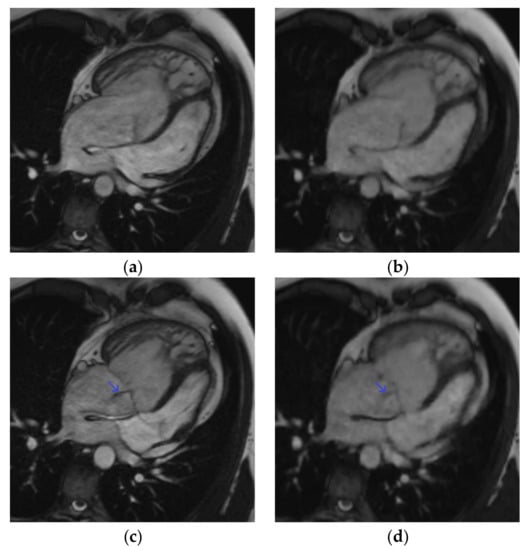

Figure 3.

Short-axis cine slice acquired with both sequences in a 26-year-old female patient referred for a tetralogy of Fallot post-repair follow-up, demonstrating an irregular heart rate. Mean heart rate = 78 ± 14 (SD) bpm (range: 51 to 107 bpm). SSFPref view in the diastole (a) and systole (c); overall image quality score = 2/4; RVEF = 51%; EDV = 148 mL. The same slices were acquired with CSrt in the diastole (b) and systole (d); overall image quality score = 3/4; RVEF = 48%; EDV = 154 mL. The fair image quality is due to the mis-triggering of artifacts in SSFPref, while CSrt provided both accurate segmentation and good image quality. Abbreviations: bpm, beats per minute; SD, standard deviation; SSFPref, reference steady-state free-precession cine; CSrt, real-time compressed-sensing cine; RVEF, right ventricular ejection fraction; EDV, end-diastolic volume.

Another interesting point is the decrease in the mis-triggering artifacts observed with CSrt (Figure 3; Video S2 (Supplementary Materials)). Even though it was not the purpose of our study and would require further dedicated studies, this finding suggests that CSrt might have an important part to play for functional or WMD evaluations in patients with irregular heart rates [33].